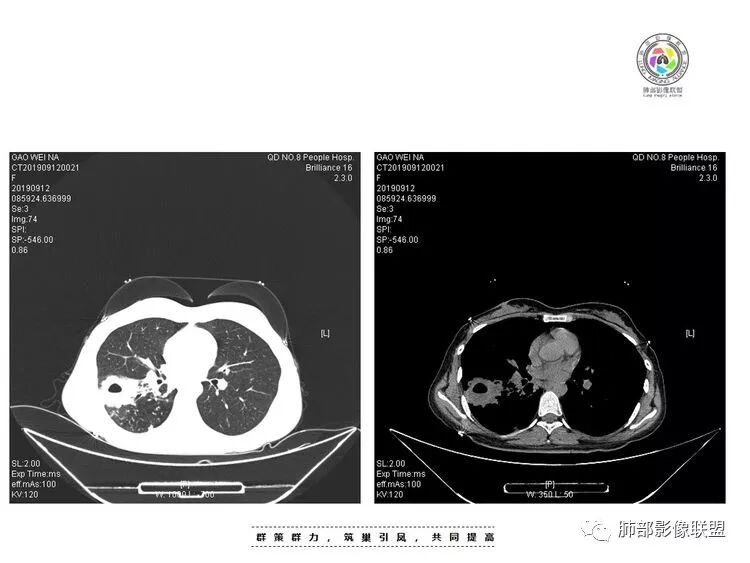

年轻女性,咳嗽咳痰(白黏痰)一月,加重一周,发热3天伴咯血。实验室:中性粒、CRP、血沉增高CT:右肺下叶不规则厚壁空洞伴散在树芽、小叶中心结节。空洞内壁光滑,似见液平。无胸腔积液及明显纵膈肿大淋巴结。给予左氧及美洛治疗12天复查CT,病灶明显吸收缩小。考虑感染没有问题。问题是单纯细菌感染还是结核感染?甚至二元?患者病史较长,临床与影像都有符合结核的表现,且左氧对结核治疗有效。因此,建议痰找抗酸杆菌,痰培养,并继续复查肺部CT。

女,28,咳嗽咳痰(白黏痰)一月,加重一周,发热3天伴咯血。实验室:WBC,中性粒、CRP、血沉增高CT:右肺下叶背段不规则厚壁空洞伴液平,内壁光滑,临近胸膜牵拉、糊墙,近端引流支气管壁厚,周围肺野散在树芽、小叶中心结节、斑片伴肺气肿,纵隔及右肺门有淋巴结,治疗后病灶缩小;考虑结核伴感染。

2.右肺下叶片状影、结节影、硬树丫。单发空洞伴液平,内壁规则,外壁较清楚。相关支气管壁增厚。

影像符合典型继发性肺结核,或者说结核它是之前已经存在的。